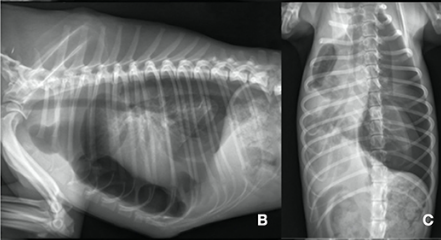

폐가 찢어지거나 기도 파열이 있는 등의 이유로 기흉이 생겼을 때 통상 반려견에서는 소량의 기흉의 경우 공기양의 증가를 모니터링 하는게 1차적이고

공기양이 증가하거나 처음확인시부터 대량으로 기흉이 존재하는 경우 차오르는 공기를 빼주는 시술을 하게 된다.

일때 단회 혹은 수회에 걸쳐 공기를 빼줌에도 불구하고 다시 차오르는 형태가 계속되거나 호흡 곤란을 유발할 정도의 공기가 차오르는 경우 흉관을 삽입하여 지속적으로 공기를 빼주게 된다.

이 증례에서는 폐야의 bulla가 파열하여 생긴 spontaneous pneumothorax 환자에서 사용한 예시라서 한번쯤 참고할만하다.